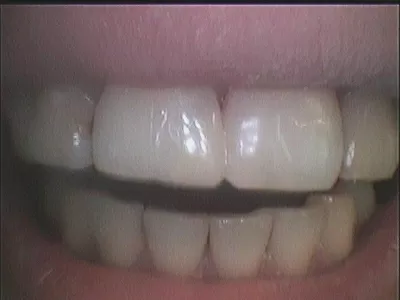

Галерея

15